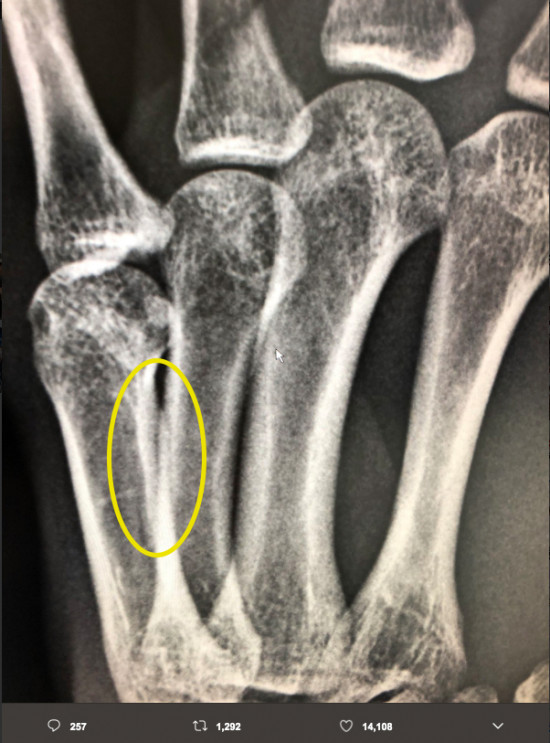

那須川のSNSの写真を編集部が整形外科の先生に見せたところ、黄色マルをした部分が骨折の可能性があるとしたが、天心の写真のパソコンの矢印マークが中央にある部分も怪しいかも。実際の手を見ないと正確なことは言えないとした。@TeppenTenshinより